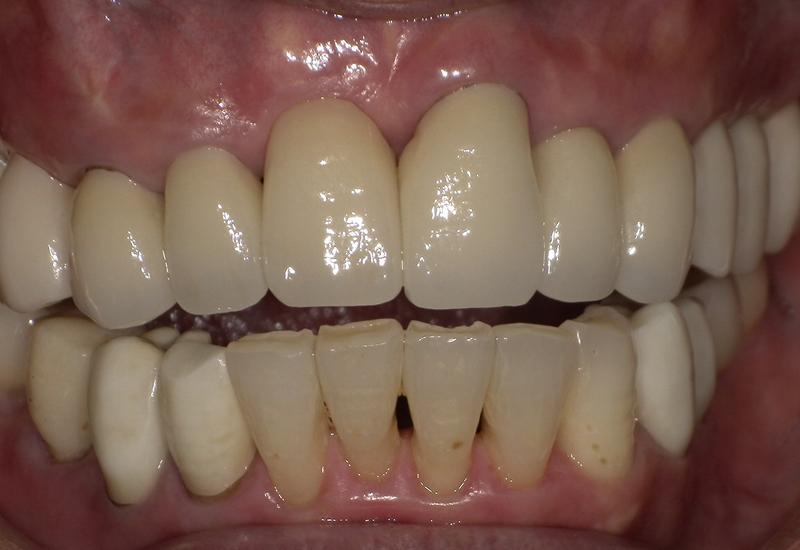

症例① シェイプメモリーアライナーによる下顎の前歯の矯正

治療期間 7ヶ月

治療時の年齢/性別 68歳 / 女性

かかった治療費 440,000円

治療方法 シェイプメモリーアライナー

注意点・詳細

• 根管治療をしてある歯はなるべく動かさない

• 下の前歯の歯の形を少しだけ小さく整えた